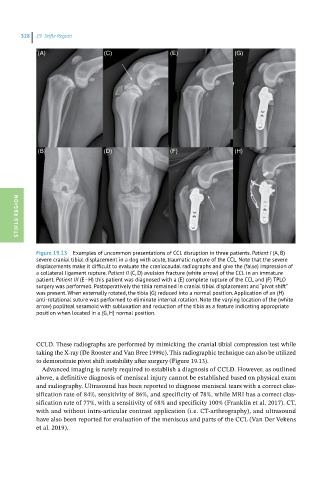

Figure 19.13 Examples of uncommon presentations of CCL disruption in three patients. Patient I (A, B)

severe cranial tibial displacement in a dog with acute, traumatic rupture of the CCL. Note that the severe

displacements make it difficult to evaluate the craniocaudal radiographs and give the (false) impression of

a collateral ligament rupture. Patient II (C, D) avulsion fracture (white arrow) of the CCL in an immature

patient. Patient III (E–H) this patient was diagnosed with a (E) complete rupture of the CCL and (F) TPLO

surgery was performed. Postoperatively the tibia remained in cranial tibial displacement and “pivot shift”

was present. When externally rotated, the tibia (G) reduced into a normal position. Application of an (H)

anti-rotational suture was performed to eliminate internal rotation. Note the varying location of the (white

arrow) popliteal sesamoid with subluxation and reduction of the tibia as a feature indicating appropriate

position when located in a (G, H) normal position.

CCLD. These radiographs are performed by mimicking the cranial tibial compression test while

taking the X-ray (De Rooster and Van Bree 1999c). This radiographic technique can also be utilized

to demonstrate pivot shift instability after surgery (Figure 19.13).